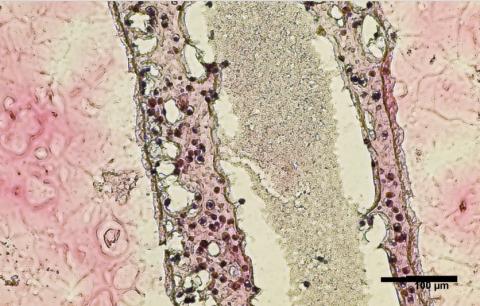

Imprimer et spécialiser des cellules de remplacement : ici, les chercheurs ont effectué une biopsie pour collecter des cellules souches des testicules d'un patient atteint d’azoospermie non obstructive. Les cellules ont été cultivées et imprimées en 3D dans ne boîte de Pétri dans une structure tubulaire creuse qui ressemble aux tubes séminifères humains producteurs de sperme (visuel). L’expérience montre que :